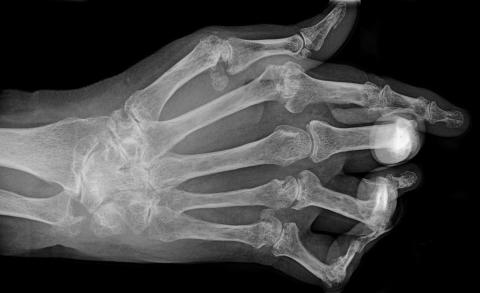

Hånd med ledødelæggelser pga. leddegigt. Nu udsættes behandlingen ikke længere, til leddene er nedbrudt.

»Man blev mere modig og tænkte, at bivirkningerne nok alligevel ikke var så voldsomme. At man måske kunne hente noget ved at sætte tidligt ind. Og det viste sig at være en god idé, for jo tidligere man starter behandlingen, desto mindre ledødelæggelse får man, og jo mere funktionsevne bevarer man«, siger Troels Mørk Hansen.